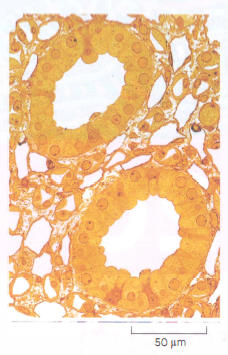

Gli organismi pluricellulari sono costituiti da comunità organizzate di cellule. Questa immagine mostra una sezione di dotto urinario del rene umano. Ogni dotto è formato da cellule “principali” fittamente organizzate in modo da formare un tubo epiteliale, che in questa sezione trasversale appare come un anello. I dotti sono immersi nella matrice extracellulare, popolata da altri tipi di cellule.